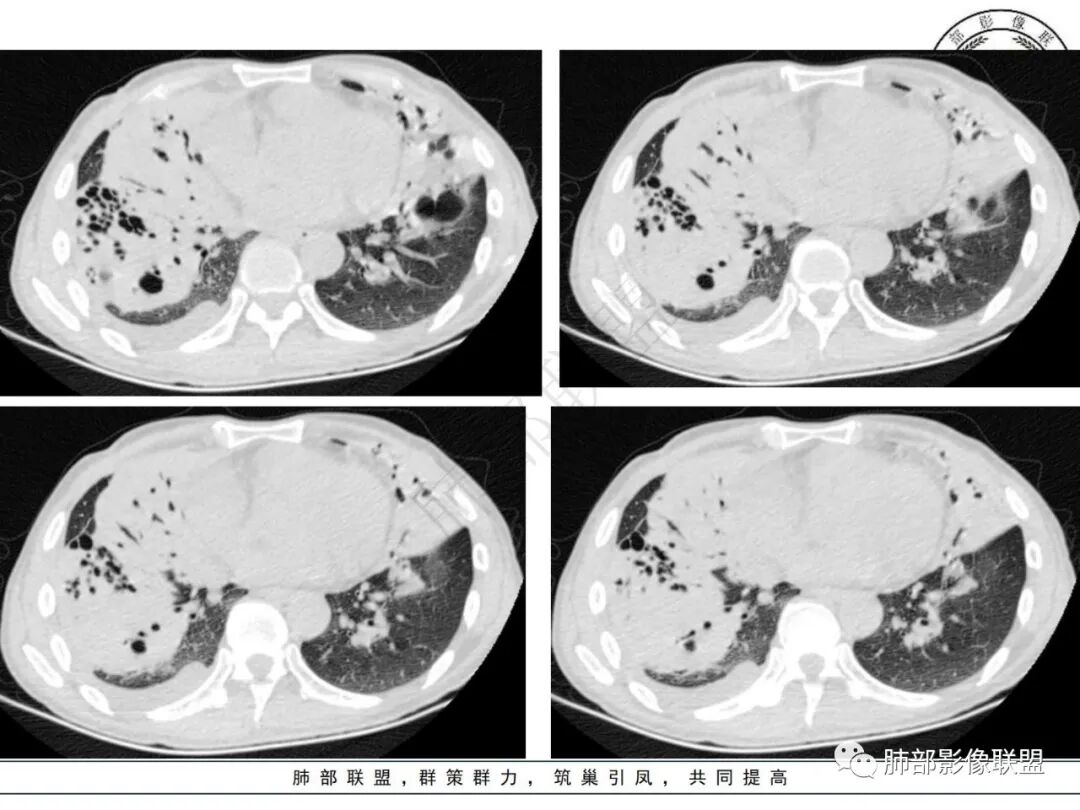

衡妈:有没有可能吸入了啥引起的感染,比如汽油。两肺门周围较大实变及囊腔型病灶,右侧实变可见扩张的支气管,夹杂磨玻璃影;左侧囊壁略厚,囊腔不规则,内多分隔,近端支气管感觉有堵塞。其余两肺散在小空洞性病灶。纵隔可见明显肿大淋巴结。先考虑感染性病变,鉴别肿瘤性病变,淋巴瘤。

张延军:右肺大片实变,边缘膨隆,上叶前段支气管阻塞,实变区内支气管扩张,左肺大的厚壁囊腔,近端见支气管进入(感觉支气管活瓣作用),右侧胸腔积液,中年男性,气促一月。恶性放前面,淋巴瘤?腺癌?(左右侧),鉴别,根据实验室检查和临床症状除外诺卡菌感染。

丽:双肺多发结节及片状实变密度影,实变内可见支气管穿行,走形僵直,部分见多发囊腔,内可见分隔,壁厚薄不均,支气管管壁略增厚,右侧胸腔积液,考虑恶性,淋巴瘤,鉴别囊腔型腺癌。

小兜:男,53岁,气促入院。CT示双肺多发实变影,右肺为著,左肺可见较大分隔囊腔,壁不均匀增厚,右肺可见多发支气管扩张伴周围实变影,右肺较大实变可见支气管截断,内可见支气管充气征,纵隔多发肿大淋巴结,综上所述考虑恶性,淋巴瘤可能。

宇宙:右肺肿块,边缘膨隆,其内支气管扩张、扭曲,少许坏死,上叶前段支气管阻塞,左肺囊腔,壁薄厚不均,其内见分隔,两肺另见多发结节,纵膈淋巴结肿大,右侧胸水,考虑腺癌,鉴别淋巴瘤。

放射线:双肺可见多发斑片状密度增高影,部分可见空泡影,右肺大片实变病灶内见支气管扩张影及斑片状低密度坏死区,边界不清,部分支气管开口阻塞,与胸壁之间少量积液,左肺上叶囊腔型病变,内部可见分隔,该患者亚急性病程,白细胞不高,无发热,考虑二元论右肺腺癌?淋巴瘤?左肺囊性腺瘤样畸形,鉴别结核,马尼。

那个人:中年男性,气促,贫血明显,C反应蛋白升高。无发热。至少从病史来看,感染可能性很低,除非隐藏了宿主因素或者特殊用药史。双肺多发斑片实变肿块影,右肺肿块影,前段支气管堵塞?其他支气管还可以,通畅扩张,坏死不明显,左肺大囊腔。整体恶性可能性大。

毛勤香:实验室检查基本阴性,两肺多发空洞,部分有分隔,右肺团片团块,右肺上叶支气管闭塞,上叶病灶上部层面感觉又不够实,淋巴结有增大,右侧胸腔少量积液,无畏寒发热,无咳嗽咳痰,整体感觉偏恶性,老年男性,右肺鳞癌并转移?鉴别腺癌和真菌感染。

1.病例特点:中年男性,气促,中长病程。贫血明显,无发热。实验室轻度异常(C反应蛋白升高)。双肺多发结节、片状影,边界可分辨,多见支气管穿行,走形僵直。左肺上叶较大囊腔,腔内分隔明显,壁薄不均,可见结节样增厚,相邻肺组织膨胀不全。右肺上叶块影巨大,多支气管穿行,前段支气管闭塞,后段支气管扩张。余支气管管壁前段增厚。右上纵隔多发肿大淋巴结。右侧胸腔积液。